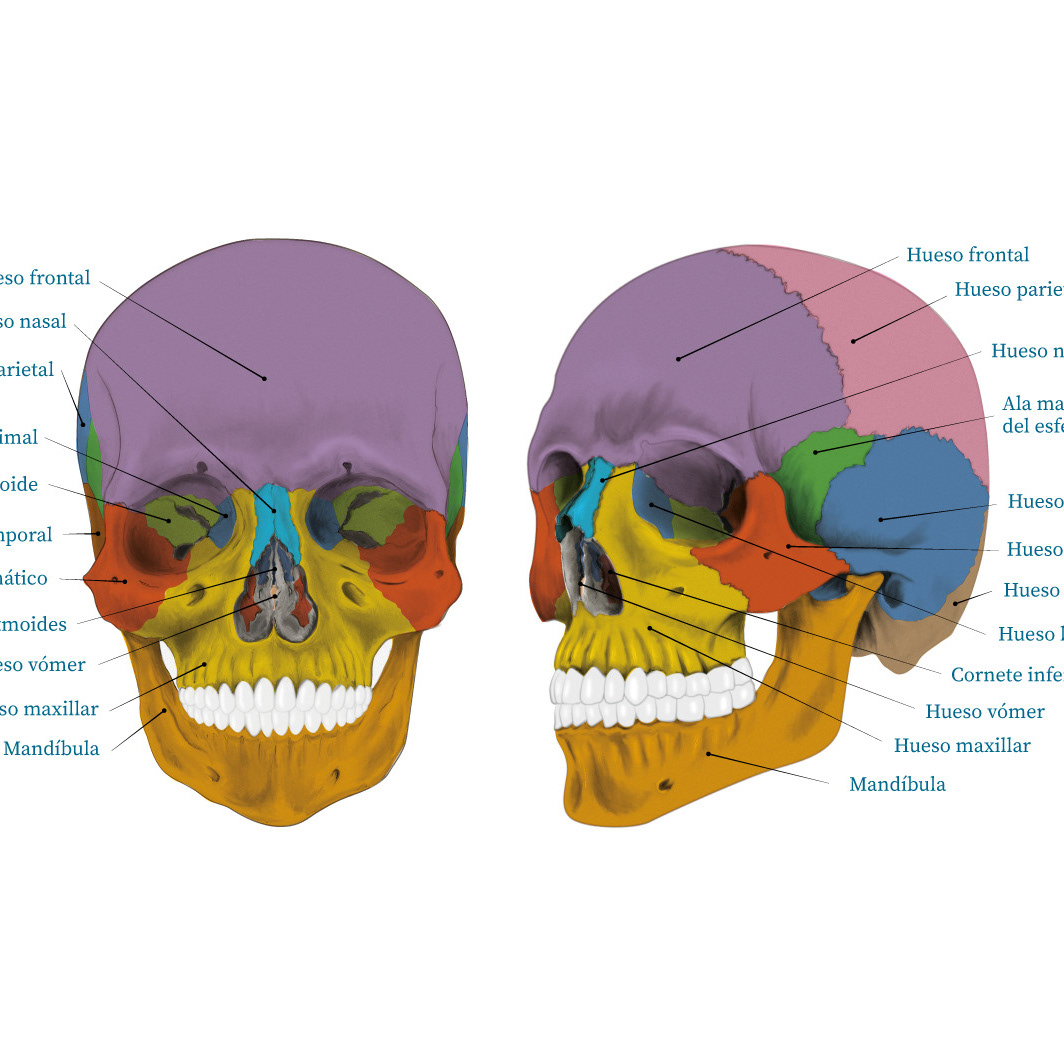

Ilustración médica / Craneos

Cráneos